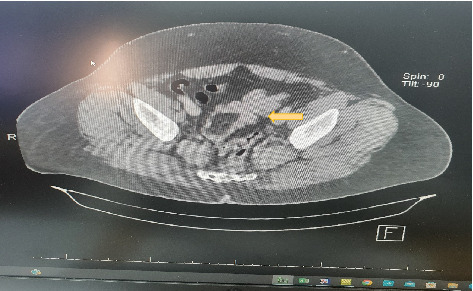

Background: Lipoma is one of the benign tumors that originate from adipose tissue, most likely in the neck, chest, back, shoulders, arms, and thighs. It is rare to find lipoma originating from submucosal adipose tissue. Colonic submucosal lipomas develop at frequency of 0.035%-4.4%. The incidence of submucosal colonic lipoma is 0.15% at colonoscopy. Intussusception is a common cause of bowel obstruction in children; however, it is rare in adults. Usually, it has a malignant background in adults. Case Presentation: A 43-year-old male presented to the hospital with a history of intermittent abdominal pain for 6 months. Pain is associated with alternating diarrhea and constipation. Physical examination showed left lower abdominal tenderness. CT scan of the abdomen showed sigmoid colo-colonic intussusception. Discussion: Colo-colonic intussusceptions account for 17% of all intestinal intussusceptions in adults, and it is most likely caused by malignant lesions rather than a submucosal lipoma. Conclusion: Submucosal lipoma is a rare cause of colo-colonic intussusceptions. It should be considered in differential diagnosis.